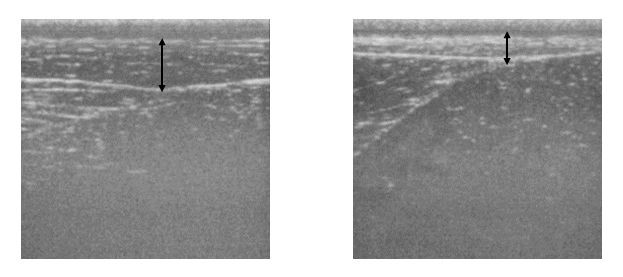

[±×¸²2] ÃÊÀ½ÆÄ °Ë»ç·Î ÃøÁ¤ÇÑ ¼­·¯ºê·¹µåÀÇ µÐºÎ Áö¹æ µÎ²². ¿ÞÂÊ ¿µ»óÀÇ µÐºÎ°¡ Áö¹æÀÌ ´õ µÎ²¨¿î °ÍÀ» º¼ ¼ö ÀÖ´Ù.

ÇöÀç ¸»ÀÇ Ã¼Áö¹æ·ü¿¡ ´ëÇÑ Á¤È®ÇÑ µ¥ÀÌÅÍ´Â ±×´ÙÁö ¸¹Áö ¾Ê´Ù. ¸»Àº »ç¶÷ÀÌ »ç¿ëÇÏ´Â °£ÀÌ Ã¼Áö¹æ ÃøÁ¤±â¸¦ »ç¿ëÇØ ÃøÁ¤ÇÏÁö ¾Ê±â ¶§¹®ÀÌ´Ù. ÃÖ±Ù ¹Ì±¹ ´ºÀúÁö ÁÖ¸³´ëÇÐÀÇ ¿¬±¸¿øÀÌ ½ºÅÄ´Ùµåºê·¹µå ǰÁ¾(Standardbred, ¼­·¯ºê·¹µå¿Í ºñ½ÁÇÑ Ç°Á¾)ÀÇ Ã¼Áö¹æ·ü ¿¬±¸ ³í¹®À» ¹ßÇ¥Çß´Ù. ´ºÀúÁö ¿¬±¸ÁøÀº ¸» µÐºÎÀÇ Áö¹æ µÎ²²¸¦ ÃÊÀ½ÆÄ °Ë»ç·Î ÃøÁ¤Çϰí(±×¸² 1, 2) Àü½ÅÀÇ Ã¼Áö¹æ·üÀ» °è»êÇØ ÃßÁ¤Çß´Ù. ¿¬±¸¿¡ µû¸£¸é, °æ±â ¼ºÀûÀÌ ÁÁÀº ½ºÅÄ´Ùµåºê·¹µå ¼ö¸»ÀÇ Ã¼Áö¹æ·üÀº Æò±Õ 7.4%, ¾Ï¸»Àº 9.9%¿´´Ù. ÇöÀç ¼­·¯ºê·¹µåÀÇ Ã¼Áö¹æ·ü¿¡ °üÇÑ ¿¬±¸´Â ÁøÇàµÇ°í ÀÖÁö ¾ÊÀ¸¸ç JRAÀÇ ¿¬±¸ ½Ã¼³¿¡¼­ µ¥ÀÌÅ͸¦ ¼öÁýÇϰí ÀÖÀ» »ÓÀÌ´Ù.

µ¥ÀÌÅ͸¦ ´ë·« Á¤¸®Çϸé, 1)Æ®·¹ÀÌ´×À» ½ÃÀÛÇϱâ ÀüÀÎ 1¼¼ °¡À»ÀÇ µÐºÎ Áö¹æ µÎ²²´Â ´ë·« 2.0~2.5cm Á¤µµ·Î, °è»êÇØ º¸¸é üÁö¹æ·üÀº 13~16% Á¤µµ´Ù. 2)¾à 1³â°£ Æ®·¹ÀÌ´×À» ½Ç½ÃÇÑ ÈÄÀÎ 2¼¼ °¡À»¿¡´Â µÐºÎÀÇ Áö¹æ µÎ²²°¡ 1.0~1.5cm Á¤µµÀ̸ç üÁö¹æ·üÀº 8~11% Á¤µµ°¡ µÈ´Ù. Æ®·¹ÀÌ´×À¸·Î Áö¹æÀÌ ÁÙ°í ÀÖ´Â °ÍÀ» º¼ ¼ö ÀÖ´Ù. 3)´õ Ȥµ¶ÇÑ Æ®·¹ÀÌ´×À» ¹ÞÀº 3¼¼ ÀÌ»óÀÇ ¸»µéÀº µÐºÎÀÇ Áö¹æ µÎ²²°¡ 1cm ÀÌÇÏ·Î ÁÙ¸ç üÁö¹æ·üµµ 5~8%±îÁö ÁÙ¾îµå´Â ¸ð½ÀÀ» º¸ÀδÙ. ÀÌ·¯ÇÑ Á¡¿¡¼­ Çö¿ª °æÁÖ¸¶ÀÇ µÐºÎ Áö¹æ µÎ²²´Â ¾Æ¸¶ 0.5cm ÀÌÇÏ¿¡ üÁö¹æ·üÀº 5% Á¤µµ¶ó°í ÃßÁ¤µÈ´Ù.